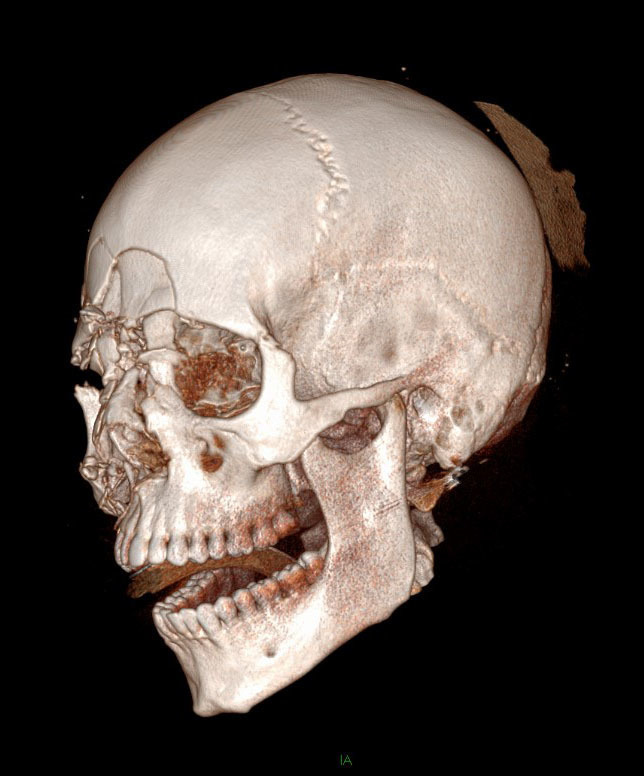

Question 4 - Il n’y a pas d’urgences neurochirurgicales sur le scanner (pas d’hématome intracrânien ni de brèche ostéoméningée). Voici les clichés de reconstruction 3D. Figure 2Figure 3Figure 4

Il y a une fracture complexe des OPN, qui s’intègre d’ailleurs dans une fracture CNEMFO

On retrouve une fracture verticale de l’hémi-maxillaire droit

Le zygoma droit est complètement détaché du bloc osseux facial. Le gauche est normal

Il n’y a aucun trait de fracture sur la mandibule

Il y a une fracture centro-faciale importante

Il y a plusieurs fractures faciales chez ce patient. On retrouve en premier lieu une fracture du CNEMFO, ainsi que deux autres fractures : fracture du zygoma droit et fracture verticale du maxillaire droit.

Rappel sur le CNEMFO : une fracture du complexe naso-éthmoïdo-maxillo-fronto-orbitaire fait suite à un choc de haute vélocité centro-facial. Le point d’impact pourrait correspondre à une fracture des os propres du nez (OPN), mais l’importance du choc entraîne un écrasement complet de la pyramide nasale et une fracture des os environnants : l’os frontal vers le haut, l’orbite (paroi médiale et plancher), la branche montante du maxillaire, et l’os éthmoïdal en arrière. Lorsque la fracture est isolée, il n’y a pas d’atteinte du zygoma.